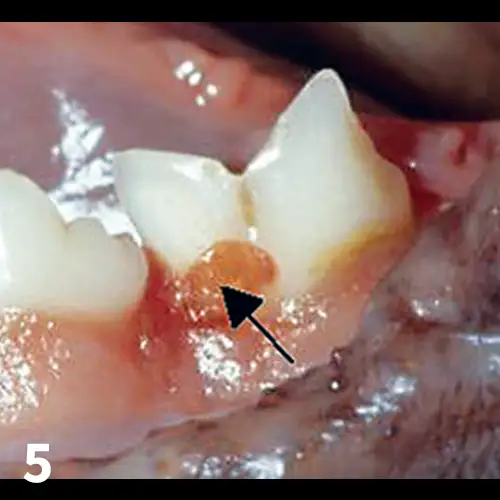

Tooth resorption is a form of external resorption. Resorption is the loss of hard tissues caused by cells called odontoclasts; external resorptions starts in the root’s cementum layer and can extend into the dentin. Previously called cervical neck lesions, feline caries, and feline odontoclastic resorptive lesions (FORLs), tooth resorption affects 25% to 75% of the cat population over age 2.11  The odontoclasts, which are derived from hematopoietic stem cells, migrate from the blood cells of the periodontal ligament space toward the external root surface and start destroying the dental hard tissue.11 (See Figures 5-7.)

Tooth resorption: Note the granulation tissue growing into the enamel defect (arrow)